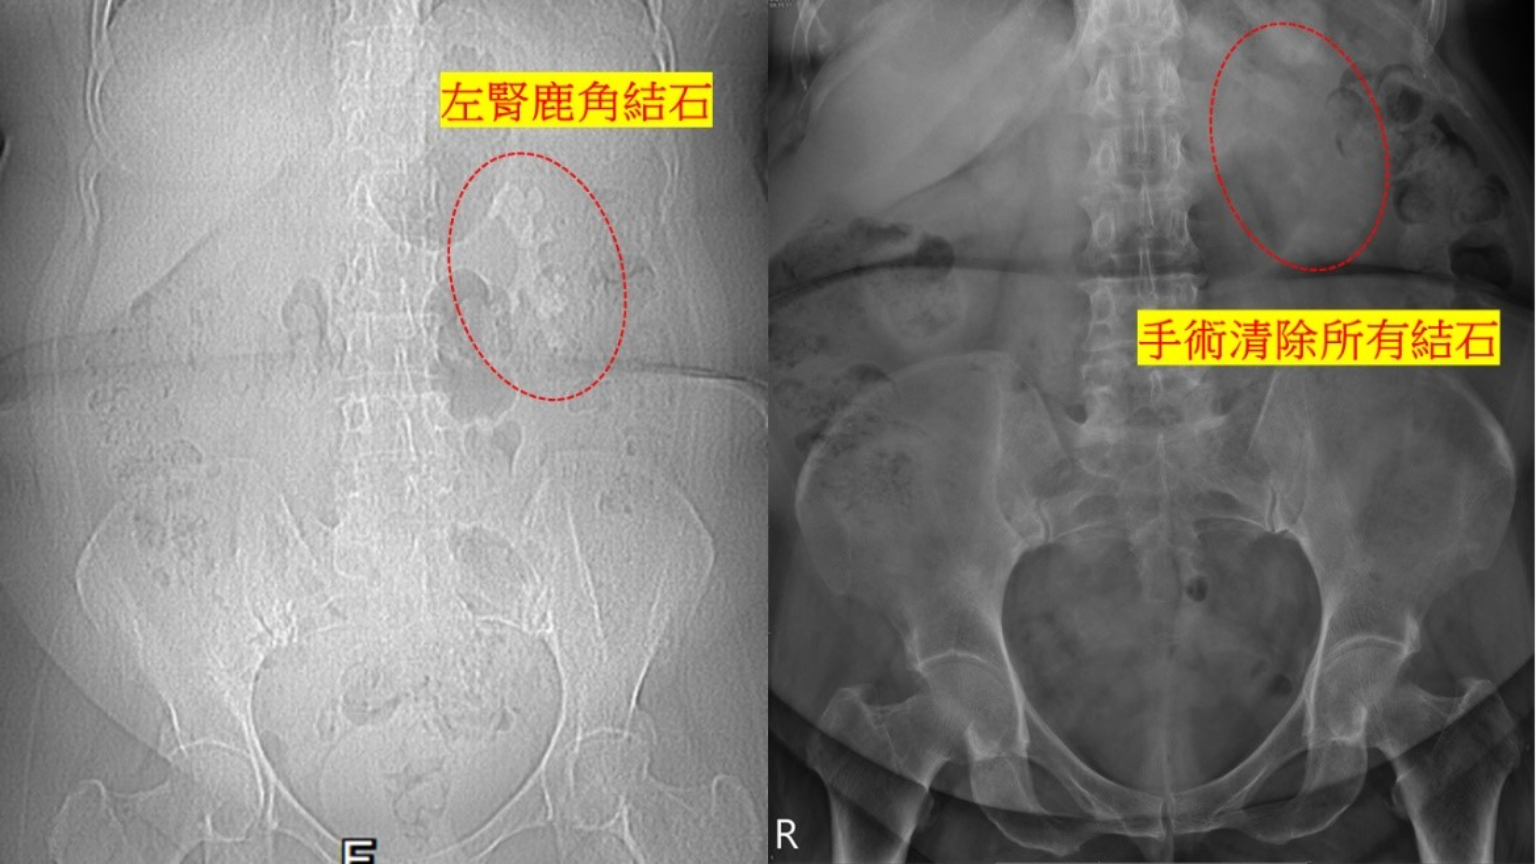

一位50餘歲女性,因左側腎臟瀰漫性巨大結石(俗稱鹿角結石),經由其他醫院轉介至本院接受軟式輸尿管鏡及迷你腎臟鏡手術(雙鏡聯合手術),順利清除所有結石。

住院中,我們發現其血清中鈣離子偏高,進一步檢查證實其副甲狀腺機能亢進。